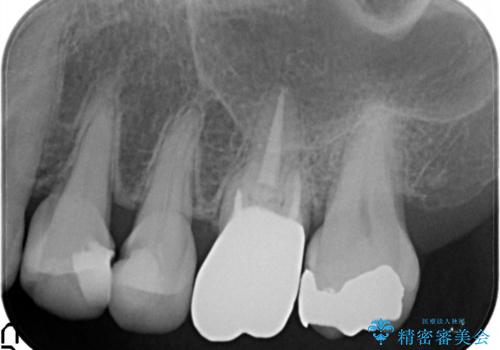

発見の難しい虫歯。根管治療から被せもの治療

- 定期検診にて被せものと歯との隙間に虫歯を発見した患者様です。

根管治療から被せもの治療(ベレッツァ)まで行いました。(根管治療は林院長に依頼)

妥協せずにすべての治療を行うことで最終的な被せものの適合を高める事ができます。